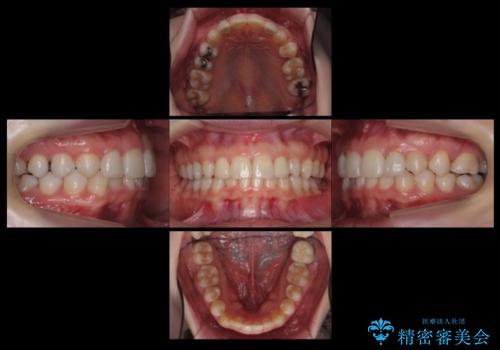

抜歯したスペースを使い、歯並びを整え、さらにその隙間を利用して細い歯を大きく整えてセラミックで被せるという総合的な治療を行いました。

マウスピース矯正→上顎両側2番のセラミック、左下67の虫歯治療 の順で行いました。

矯正治療→ホワイトニング→セラミック の順で行なっています。

ホワイトニングで綺麗に白くした歯に合わせて、被せています。